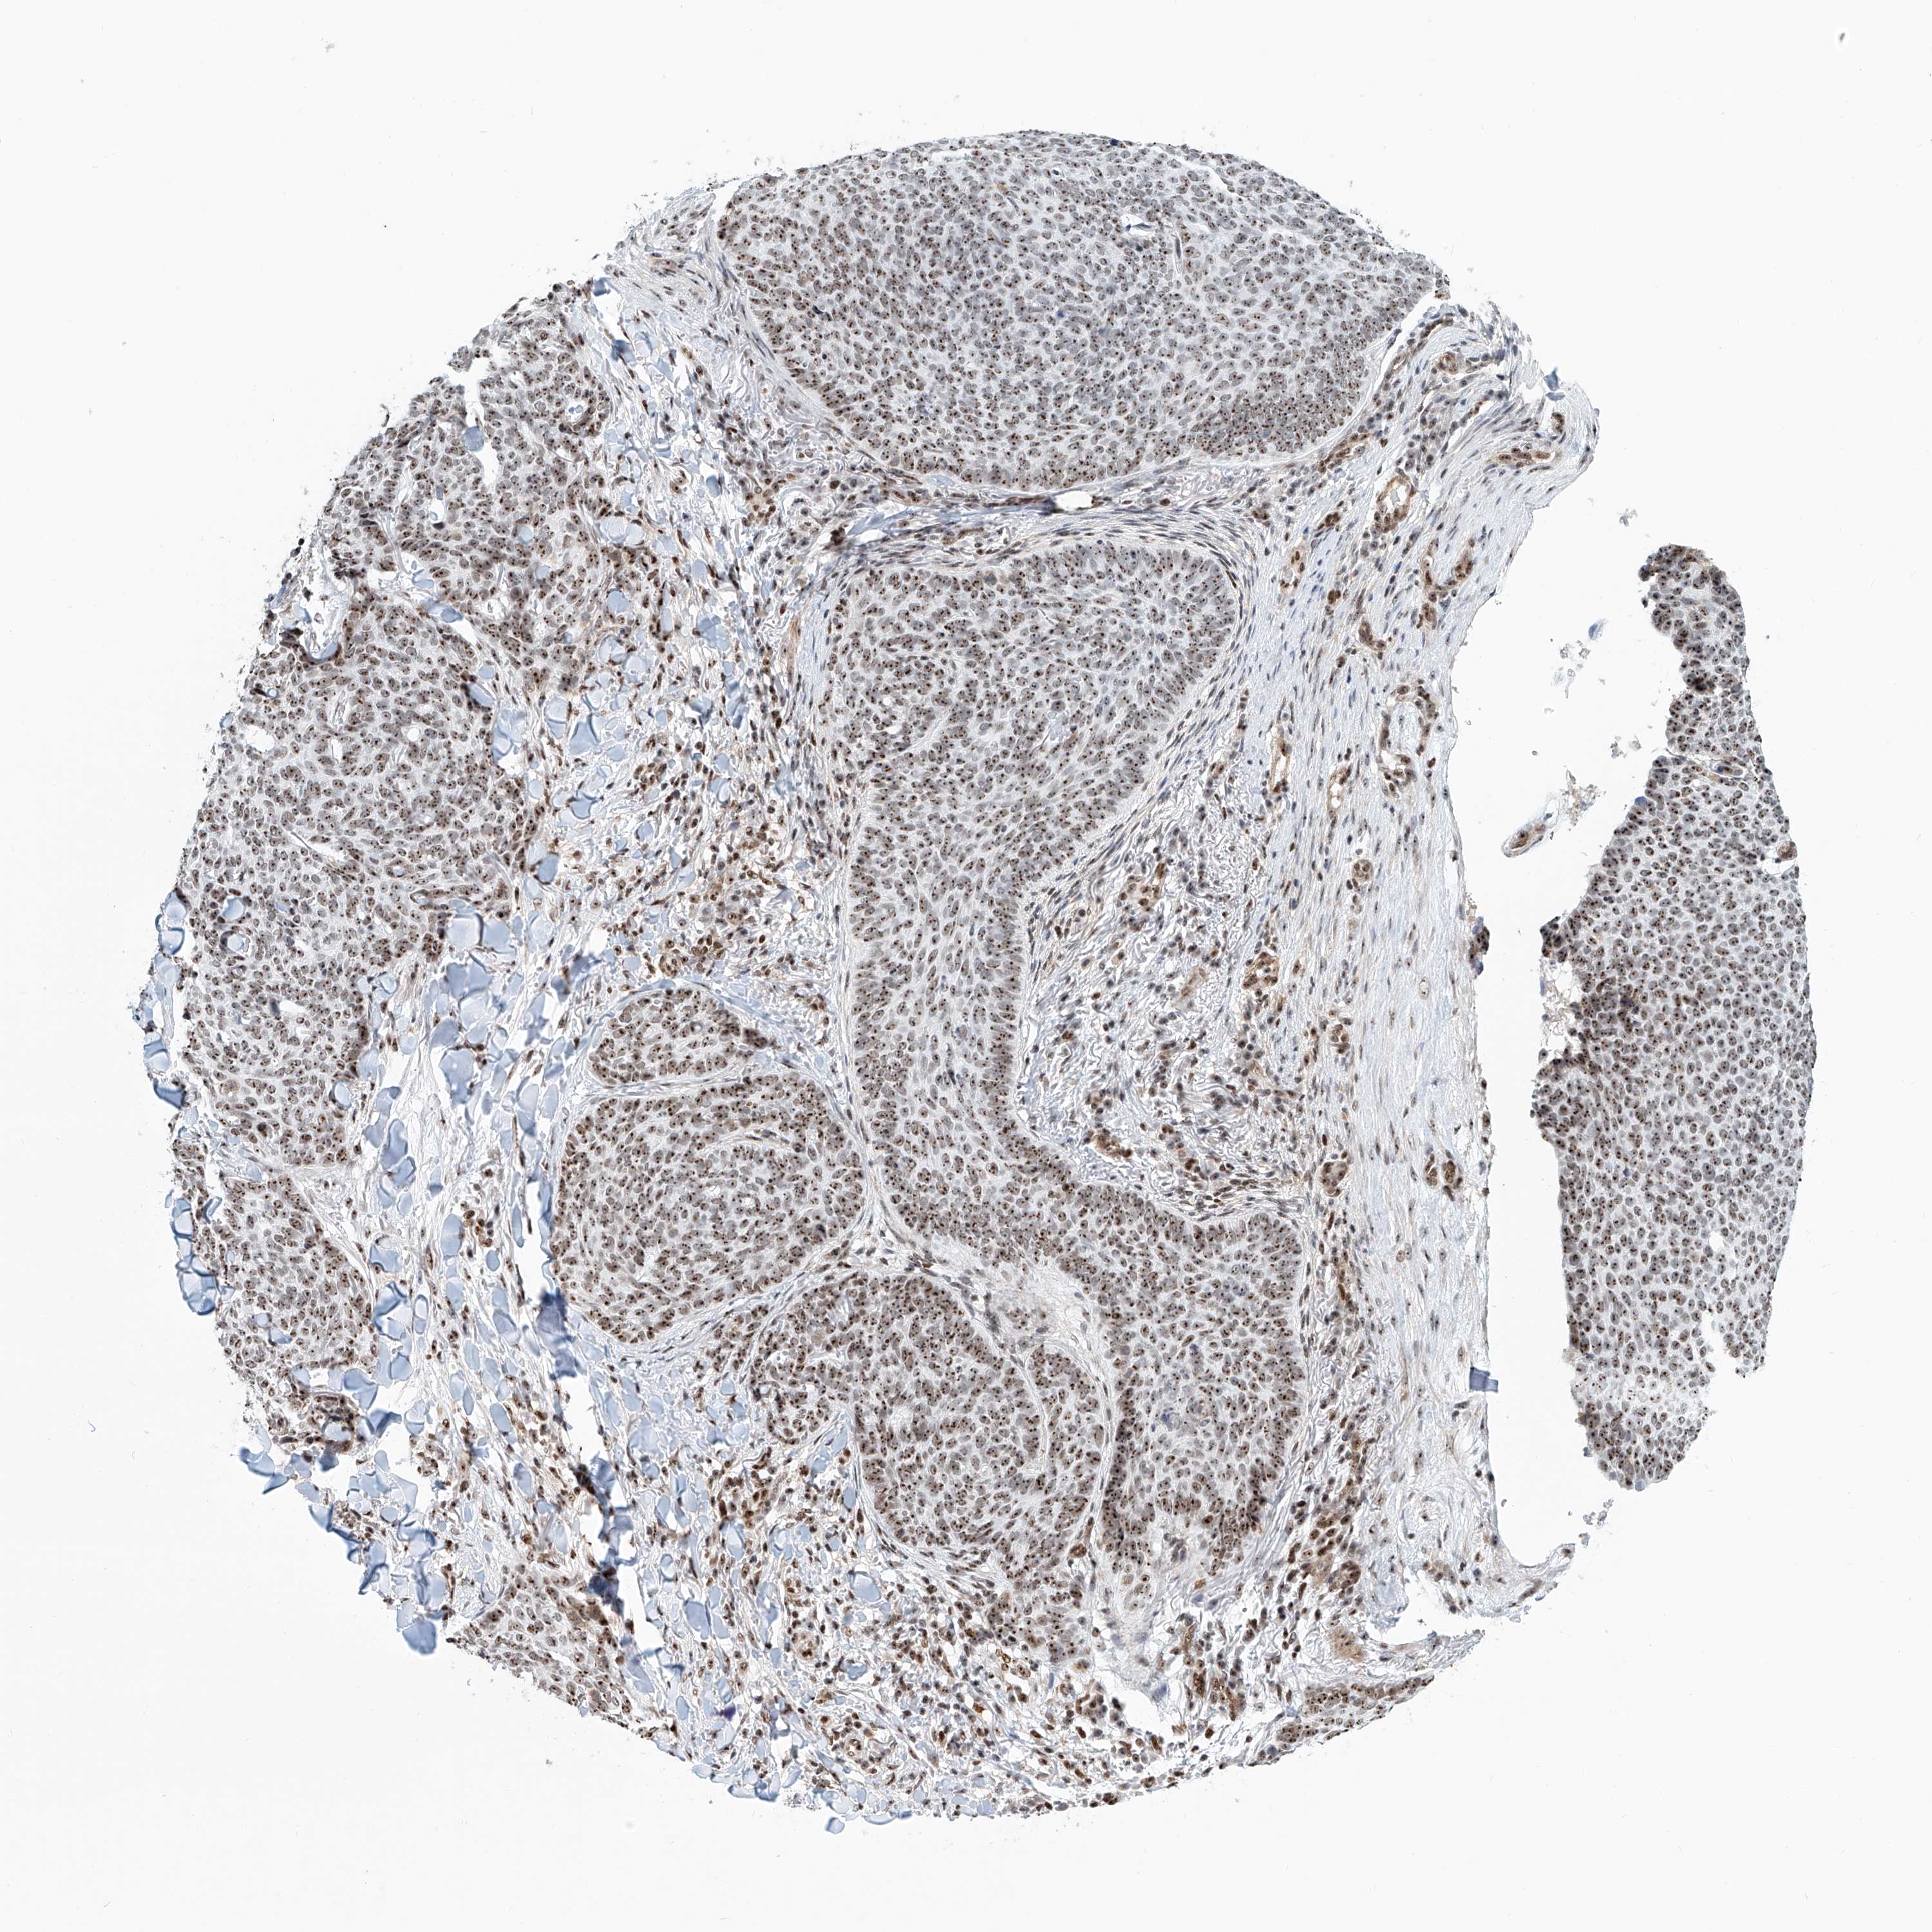

SKIN CANCER - Protein expressioni

A mouse-over function shows sample information and annotation data. Click on an image to view it in a full screen mode. Samples can be filtered based on level of antibody staining by selecting one or several of the following categories: high, medium, low and not detected. The assay and annotation is described here.

Each image is clickable and will lead to virtual microscopy that enables deeper exploration of all samples and also displays staining intensity scores, fraction scores and subcellular localization as well as patient and tissue information for each sample.

Antibody HPA031079

Staining

Medium

Intensity

Moderate

Quantity

75%-25%

Location

Cytoplasmic/membranous

Squamous cell carcinoma, metastatic, NOS